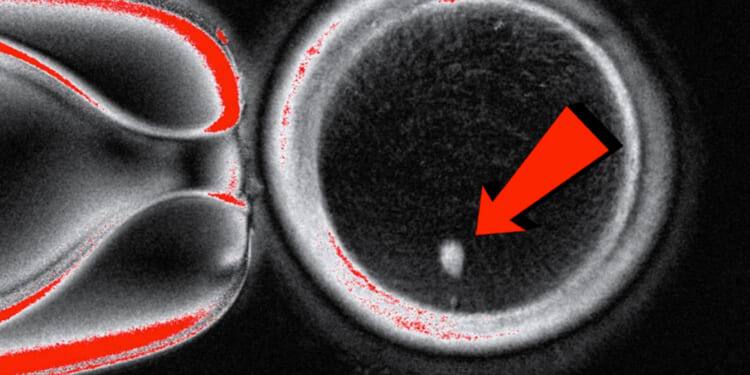

For the first time, researchers say they’ve created human eggs from skin cells—a breakthrough that raises enormous ethical, moral, and biblical concerns.

The technique could open the door for same-sex couples to have children genetically related to both partners, and could also help women unable to produce viable eggs. Lead researcher Shoukhrat Mitalipov explained, “This technology would allow many of these women to have genetically their own eggs and to have a genetically related child.”